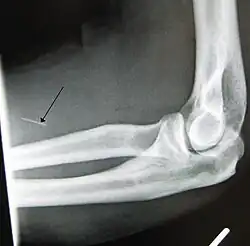

Fragment of a hypodermic needle stuck inside the arm of an IV drug user (x-ray)